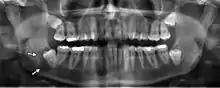

تتمتع الصور الشعاعية البانورامية بالقدرة على إظهار جزء من الرقبة وعرض التصلب الشرياني (التكلسات في الشريان السباتي) والتي تعتبر مؤشراً على كل من تصلب الشرايين الموضعي والعام. يعد تصلب الشرايين التاجية الذي يؤدي إلى احتشاء عضلة القلب (النوبة القلبية) وتصلب الشرايين السباتية التي تؤدي إلى السكتة الدماغية هي السبب الأول و الأكثر شيوعًا للوفاة في الولايات المتحدة.[5]

عدوى الأسنان وتصلب الشرايين

يعزى تصلب الشرايين إلى عوامل خطر تشمل تدخين السجائر، وفرط شحميات الدم، والسمنة، وداء السكري، وارتفاع ضغط الدم. مع ذلك هذه العوامل لا تمثل بالكامل خطر الإصابة بالمرض. تم تصوُّر تصلب الشرايين على أنه نتيجة التهاب مزمن لإصابة الخلايا البطانيةy[23] والاختلال الوظيفي الذي ربما ينجم عن عدوى الأسنان المزمن. في عام 2010 وباستخدام مؤشر التصوير الشعاعي البانورامي Mattila الذي تم التحقق منه سابقاً لقياس إجمالي العدوى السنية (على سبيل المثال، الآفات المحيطة بقمة الجذر وبين الجذور، التهاب ما حول التاج، جذور الأسنان المصابة بالتسوس، الأسنان مع تسوس وصل للب السن، العيوب العظمية الرأسية)، حددت مجموعة فريدلاندر أن الأفراد الذين يكون لديهم تصلب الشريان السباتي على صورهم البانورامية كان عندهم كميات أكبر من عدوى / التهاب أسنان من عوامل خطر تصلب الشرايين بكثير.[24]قالب:Primary source inline[25]قالب:Primary source inline في حين كان مؤشر Mattila قد استخدم سابقاً لربط مدى انتشار العدوى السنية بـمرض الشريان التاجي، فإن هذا البحث هو الأول الذي يربط بين مجموعة كاملة من أمراض الأسنان التي تقيس الصور الشعاعية البانورامية التي تثبت تصلب الشريان السباتي المتكلس.